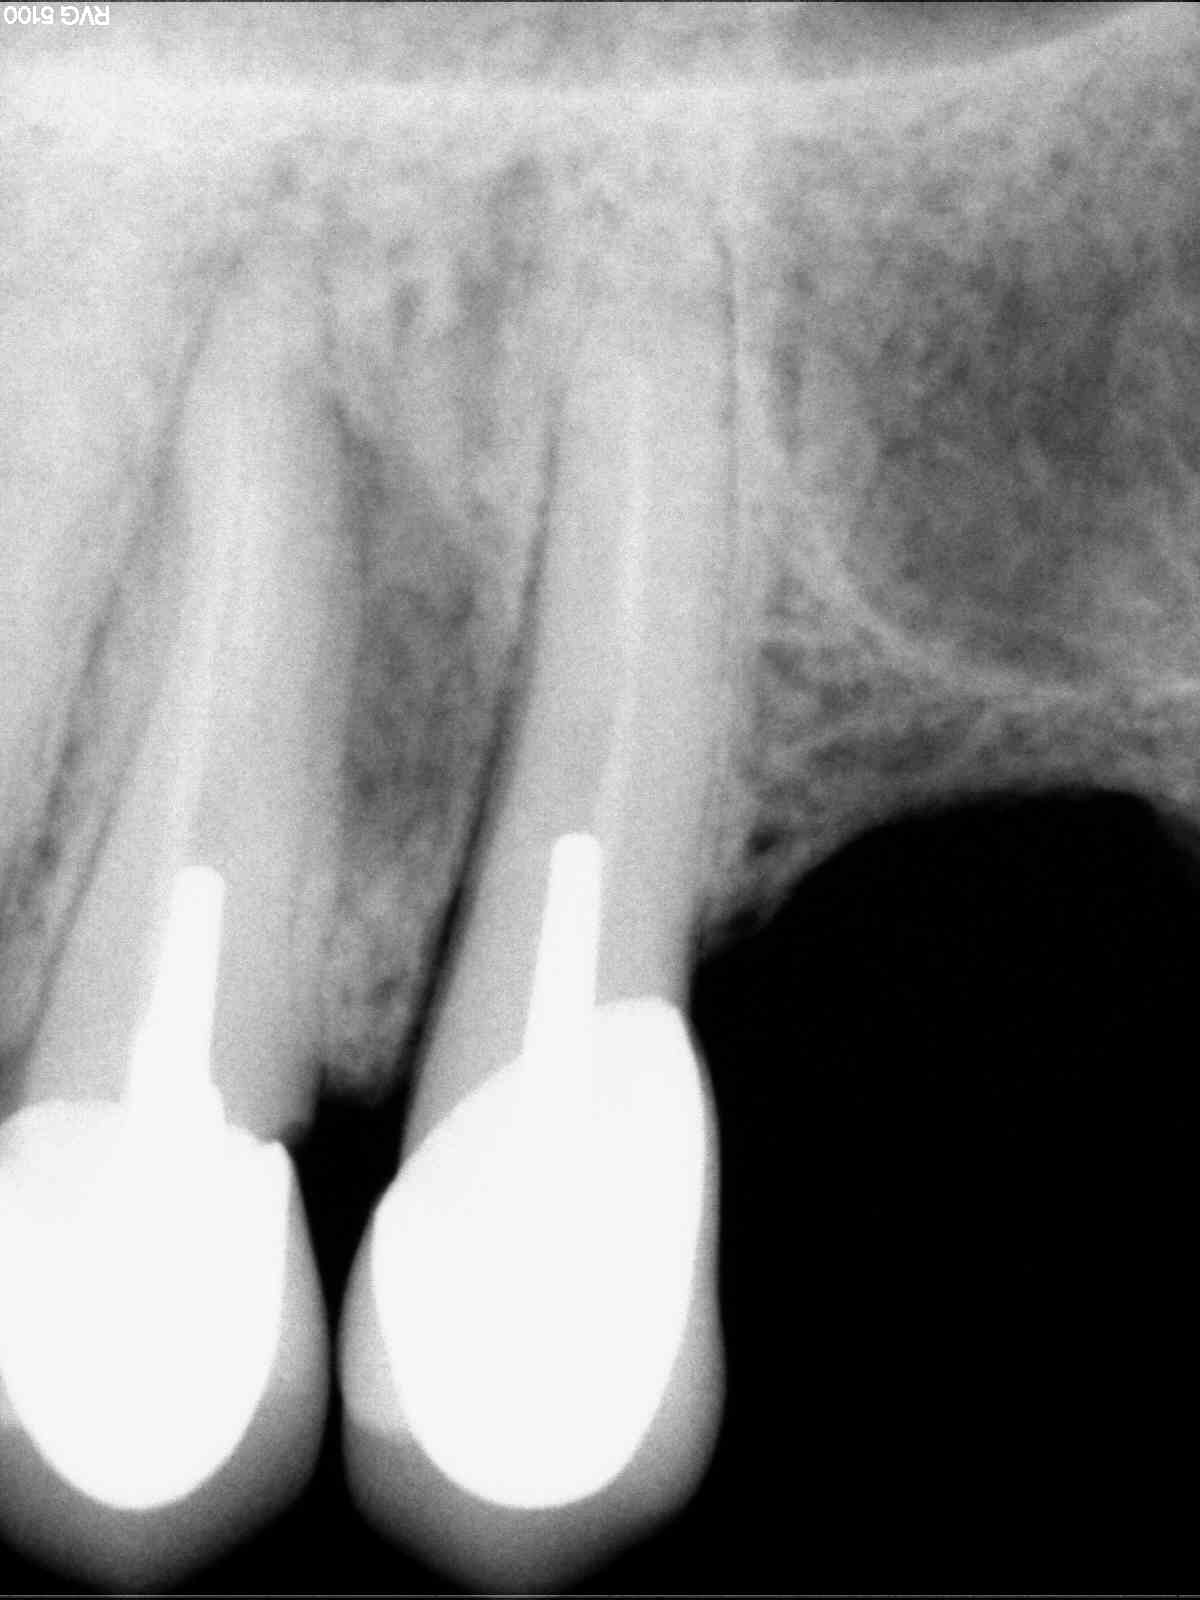

Radios1 dxb8my - Eugenol

Radios2 kprrcu - Eugenol

Radios3 auio0x - Eugenol

Radios4 pfsefa - Eugenol

Radios5 uwurgt - Eugenol

Radios6 ycayfo - Eugenol

Des inlay core... Des endos moisies... C est un français.

maladie dentaire diffuse + antécédent de choc (11 racine fracturée)